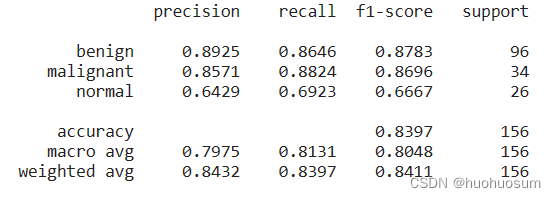

在测试集上评估模型效果,精确率、召回率等指标如下图所示:

从结果可以看出,除了normal类型预测f1-score比较低外,其他两类的指标值均接近0.9,说明例程的模型也可以用于乳腺超声数据集。